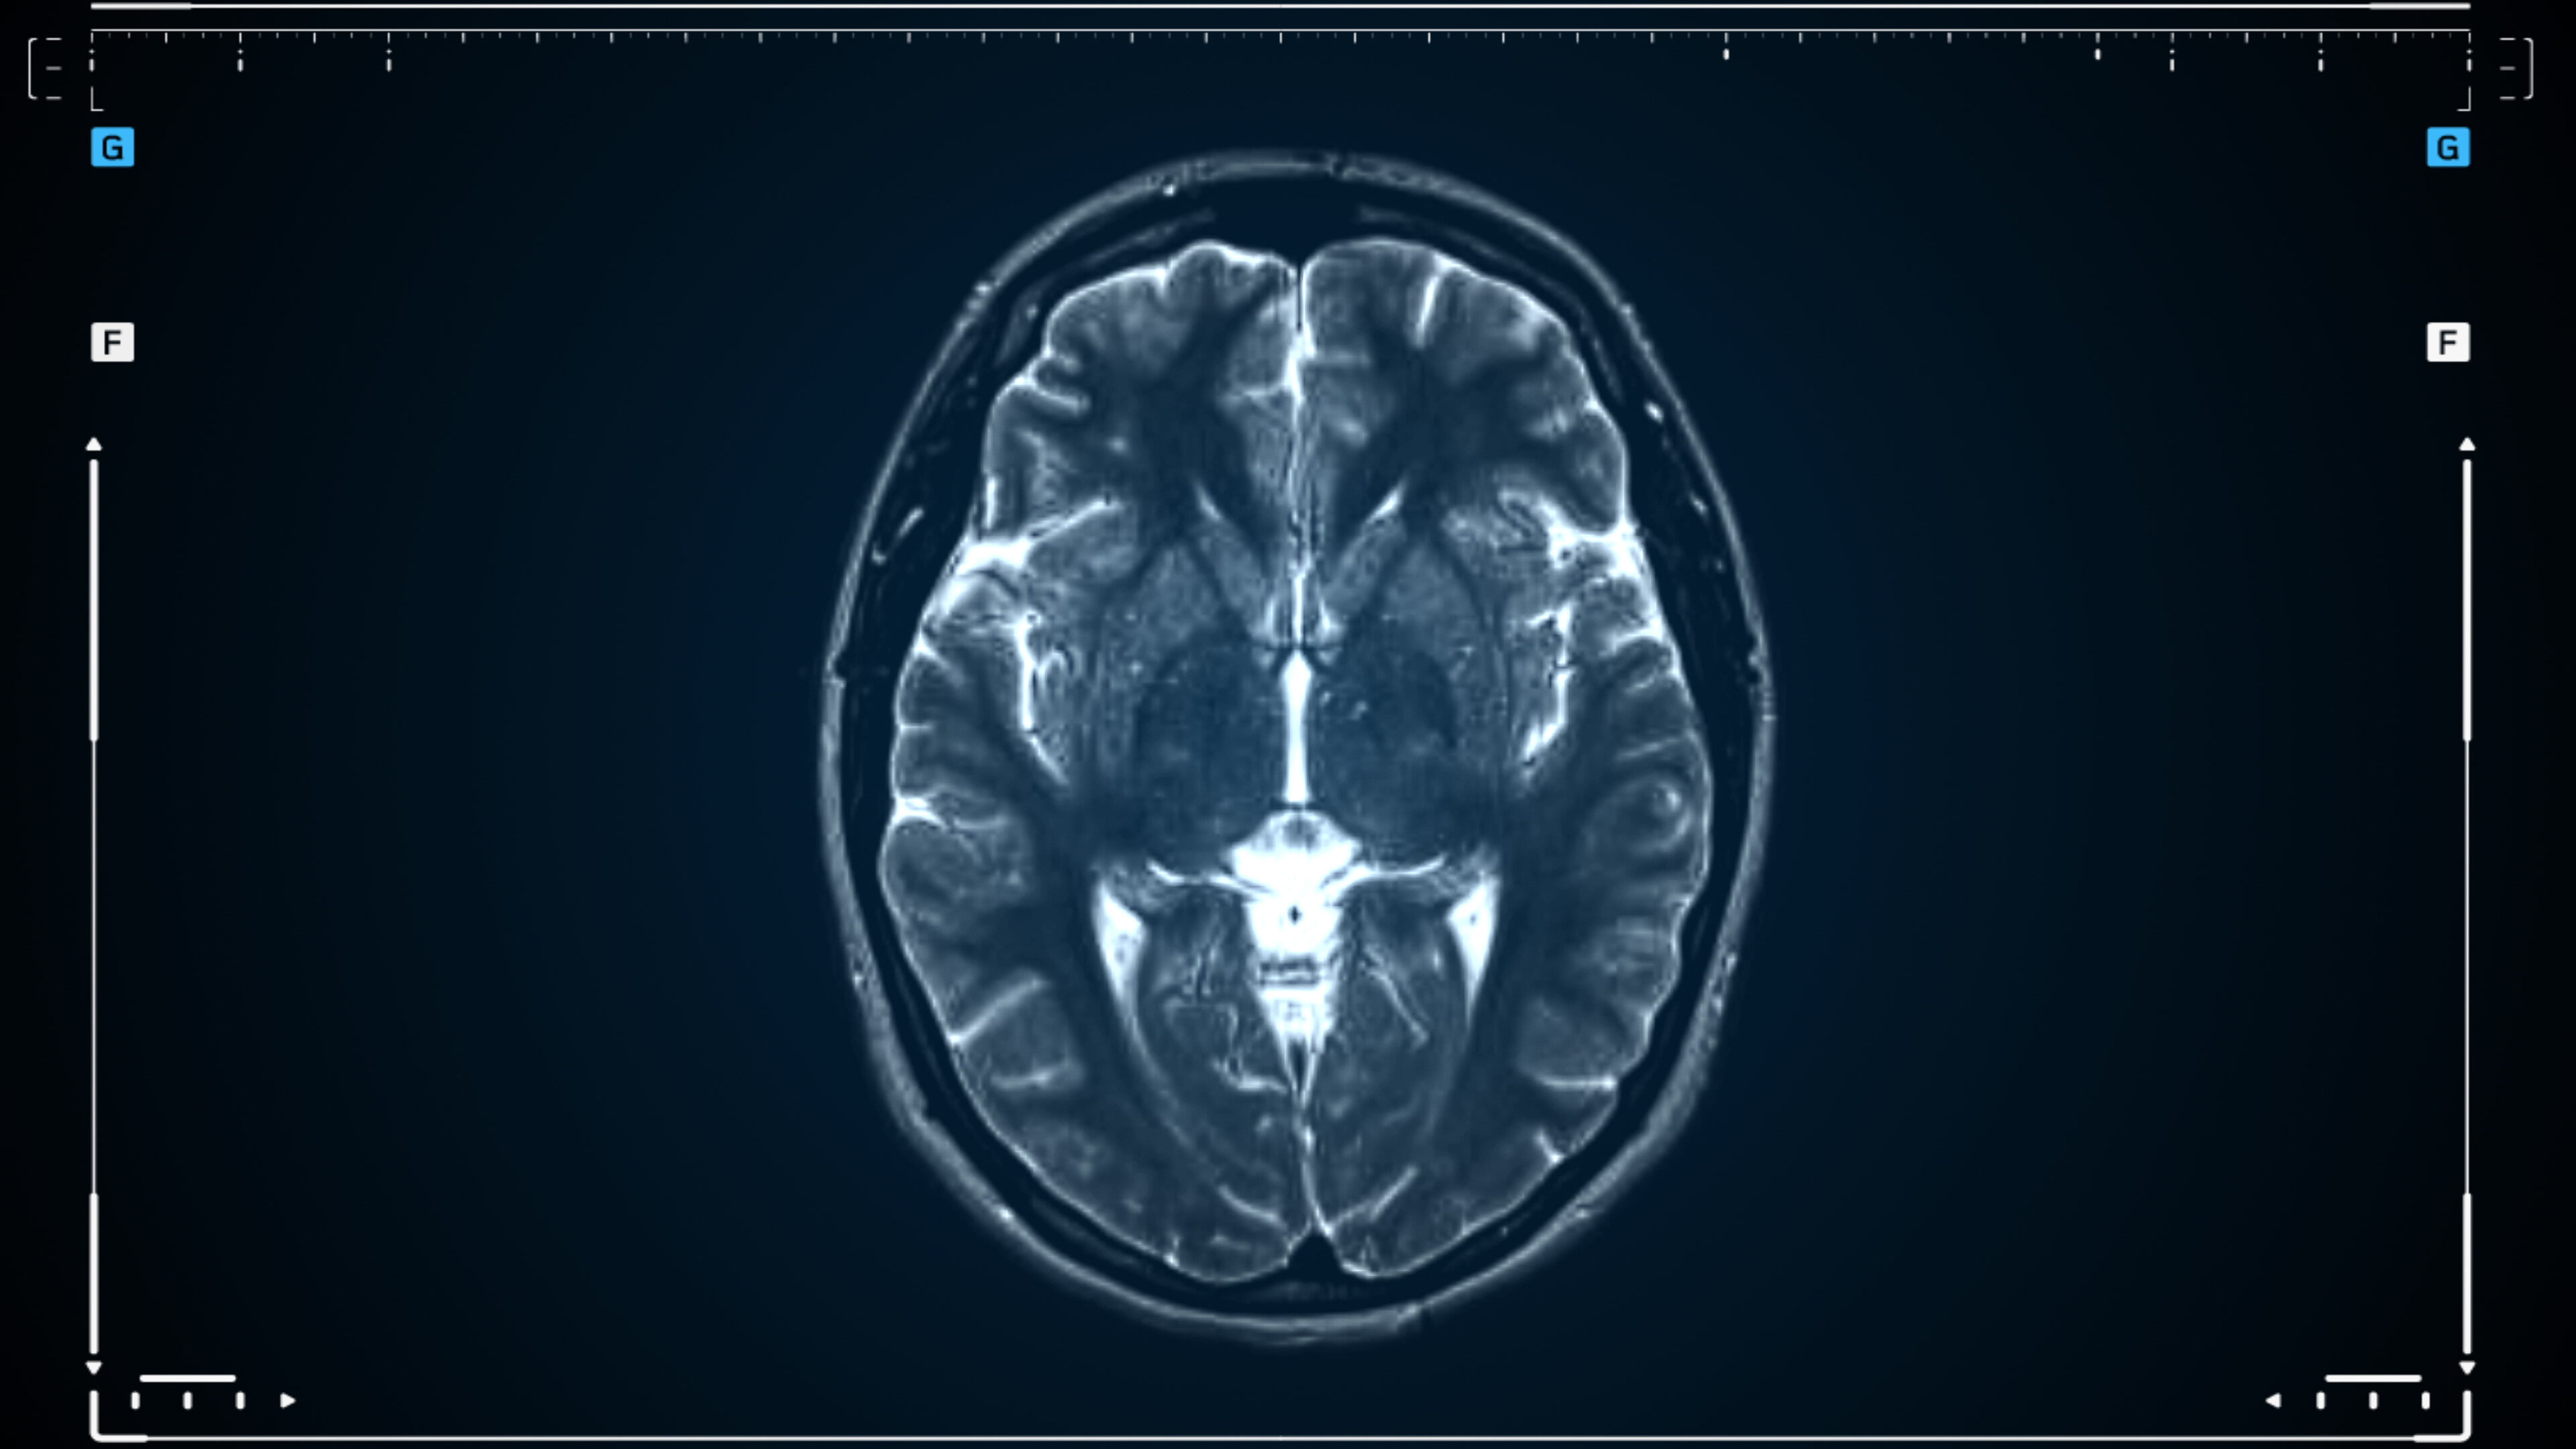

The medical diagnosis of shaken baby syndrome, or abusive head trauma (SBS/AHT), arose from a hypothesis developed in the early 1970s. Over the decades, it has led to thousands of criminal court convictions and family court determinations taking children from their parents. The National Center on Shaken Baby Syndrome claims that law enforcement authorities process at least 1,300 SBS/AHT cases per year. The diagnosis has attained iconic status within the medical specialty of child abuse pediatrics. Yet, for the past few decades, outside of the child abuse pediatrics specialty, the scientific, medical, and legal literature has been replete with challenges to the reliability of the diagnosis. With the first-in-the-nation execution of Robert Roberson based on the SBS/AHT diagnosis scheduled two weeks from now in Texas, the trustworthiness of the diagnosis is increasingly relevant. A panel of medical and forensic science experts will examine the issue in depth.